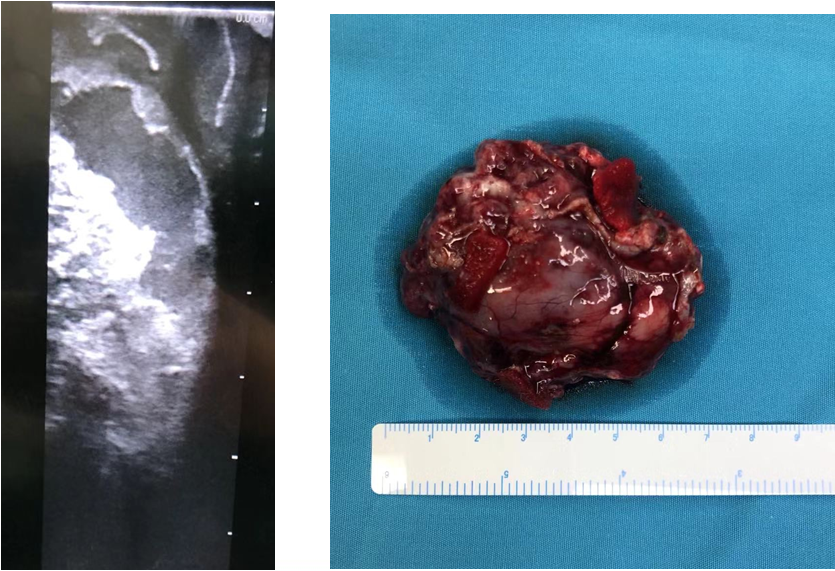

术中彩超及标本

术中肿瘤囊液